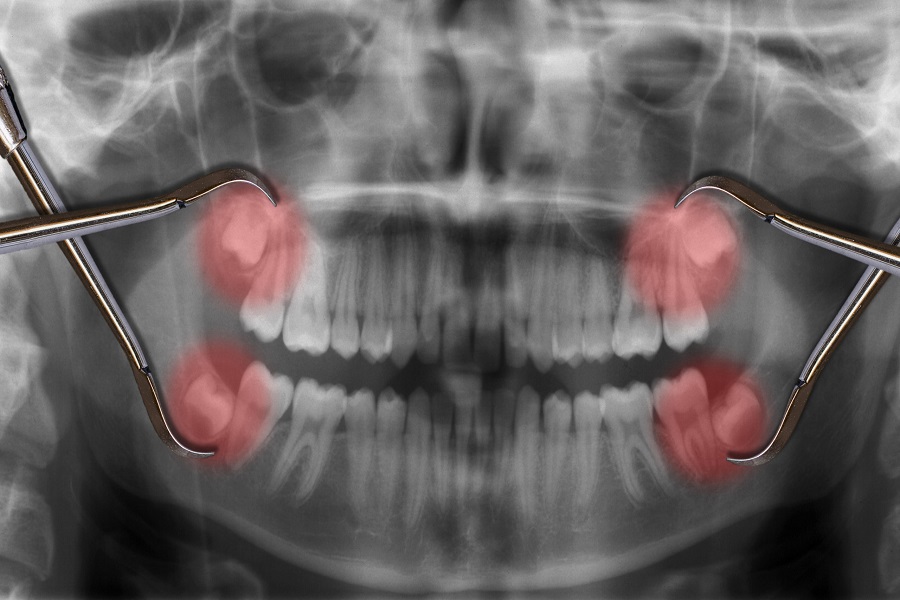

Wisdom tooth pericoronitis refers to the inflammation of the soft tissue around the tooth crown during the eruption of the third molar, and the impacted third molar is the main cause of pericoronitis. Due to the degeneration and shortening of the jaw during human evolution, there is not enough space for the eruption of the third molar… Wisdom tooth “pericoronitis” refers to the inflammation of the soft tissue around the crown during the eruption of the third molar, and the resistance of the third molar Birth is the main cause of pericoronitis.

Due to the degeneration and shortening of the jaw during the evolution of human beings, the third molars did not have enough position to erupt and were impacted. In clinical practice, vertical impaction of partial eruption and mesial oblique impaction are the most common, and crowns with incomplete eruption are the most common. Most of them are located below the plane of the second molar, and the impacted part is covered by the gingival flap to form a breeding bag. The food residues and bacteria hidden in the breeding bag are not easy to be removed when rinsing and brushing. Injury from other causes can reduce local resistance and cause a large number of bacteria to multiply. Combined with factors such as colds, lack of sleep, excessive fatigue, women’s menstrual cycle and other factors that reduce systemic resistance, it can cause sudden onset of pericoronitis.